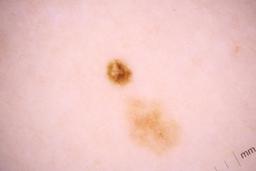

ISIC_8336318

Clinical

| Field | Value |

|---|---|

| age_approx | 40 |

| anatom_site_1 | Trunk |

| anatom_site_2 | Anterior trunk |

| anatom_site_3 | Anterior abdomen |

| clin_size_long_diam_mm | 6.19 |

| diagnosis_1 | Malignant |

| diagnosis_2 | Malignant melanocytic proliferations (Melanoma) |

| diagnosis_3 | Melanoma Invasive |

| diagnosis_4 | Melanoma Invasive, Superficial spreading |

| diagnosis_confirm_type | histopathology |

| image_manipulation | instrument only |

| image_type | TBP tile: close-up |

| lesion_id | IL_5097969 |

| mel_thick_mm | 0.40 |

| patient_id | IP_8989787 |

| sex | male |

| tbp_tile_type | 3D: white |